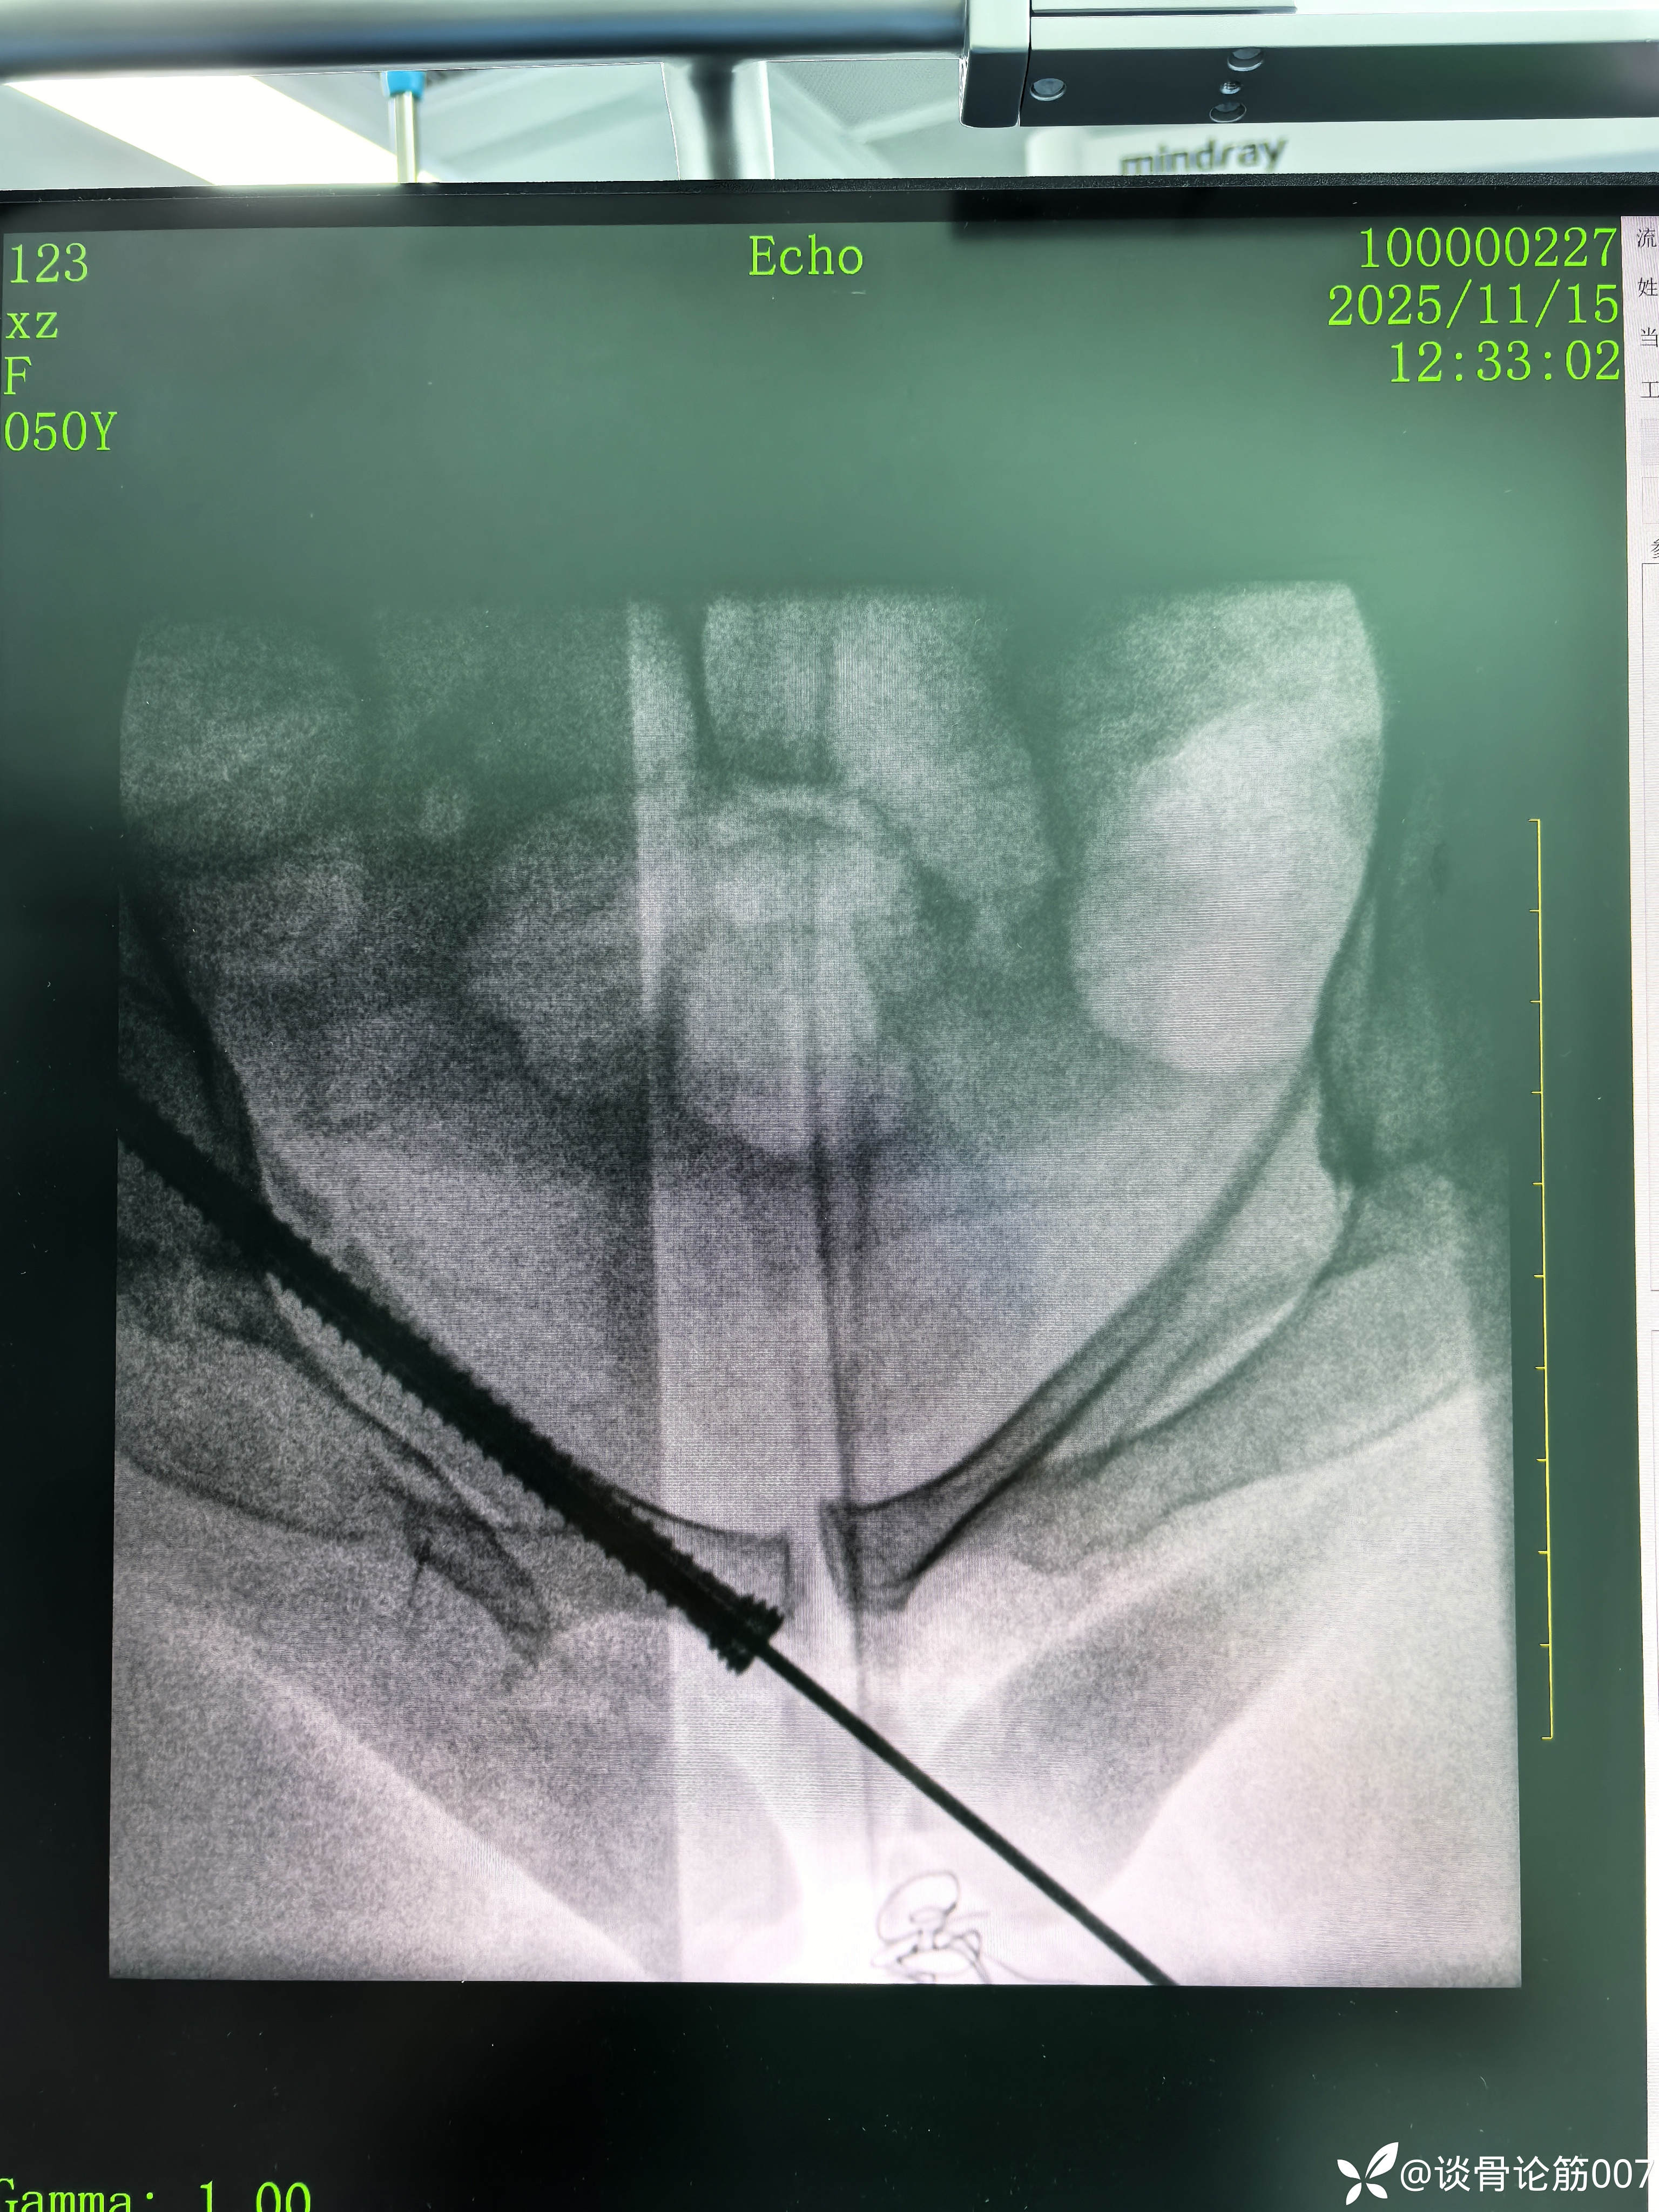

骶髂螺钉+耻骨上支螺钉实操

骨盆B型骨折,给予闭合复位骶髂螺钉+耻骨上支螺钉固定。

虽然术前进行导泄,通便,但腹部仍有积气,对透视还是有一定影响

从结果来看,进针点应用粗钢针位置可能刚好一点

女性耻骨上支确实比较细

耻骨上支螺钉通道有限,如果有5.0空心螺钉更方便,但5.0螺钉没有长的,3.5长螺钉对耻骨上支骨折复位作用差一点,因为是实心,对操作要求更高一点。